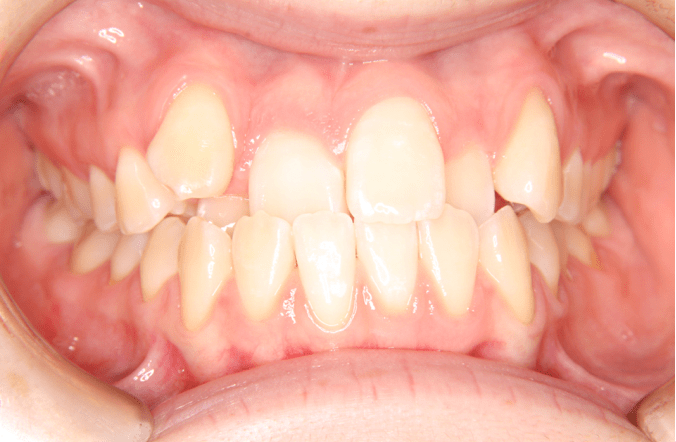

受け口とは、上下の歯の噛み方が逆になっている状態のことを言います。本来、上の歯が下の歯を覆う形で咬合していますが、受け口は下の歯が前にある状態のことです。

矯正歯科用語で言うと、「反対咬合(はんたいこうごう)」と言います。

前歯の噛み方が逆になっています